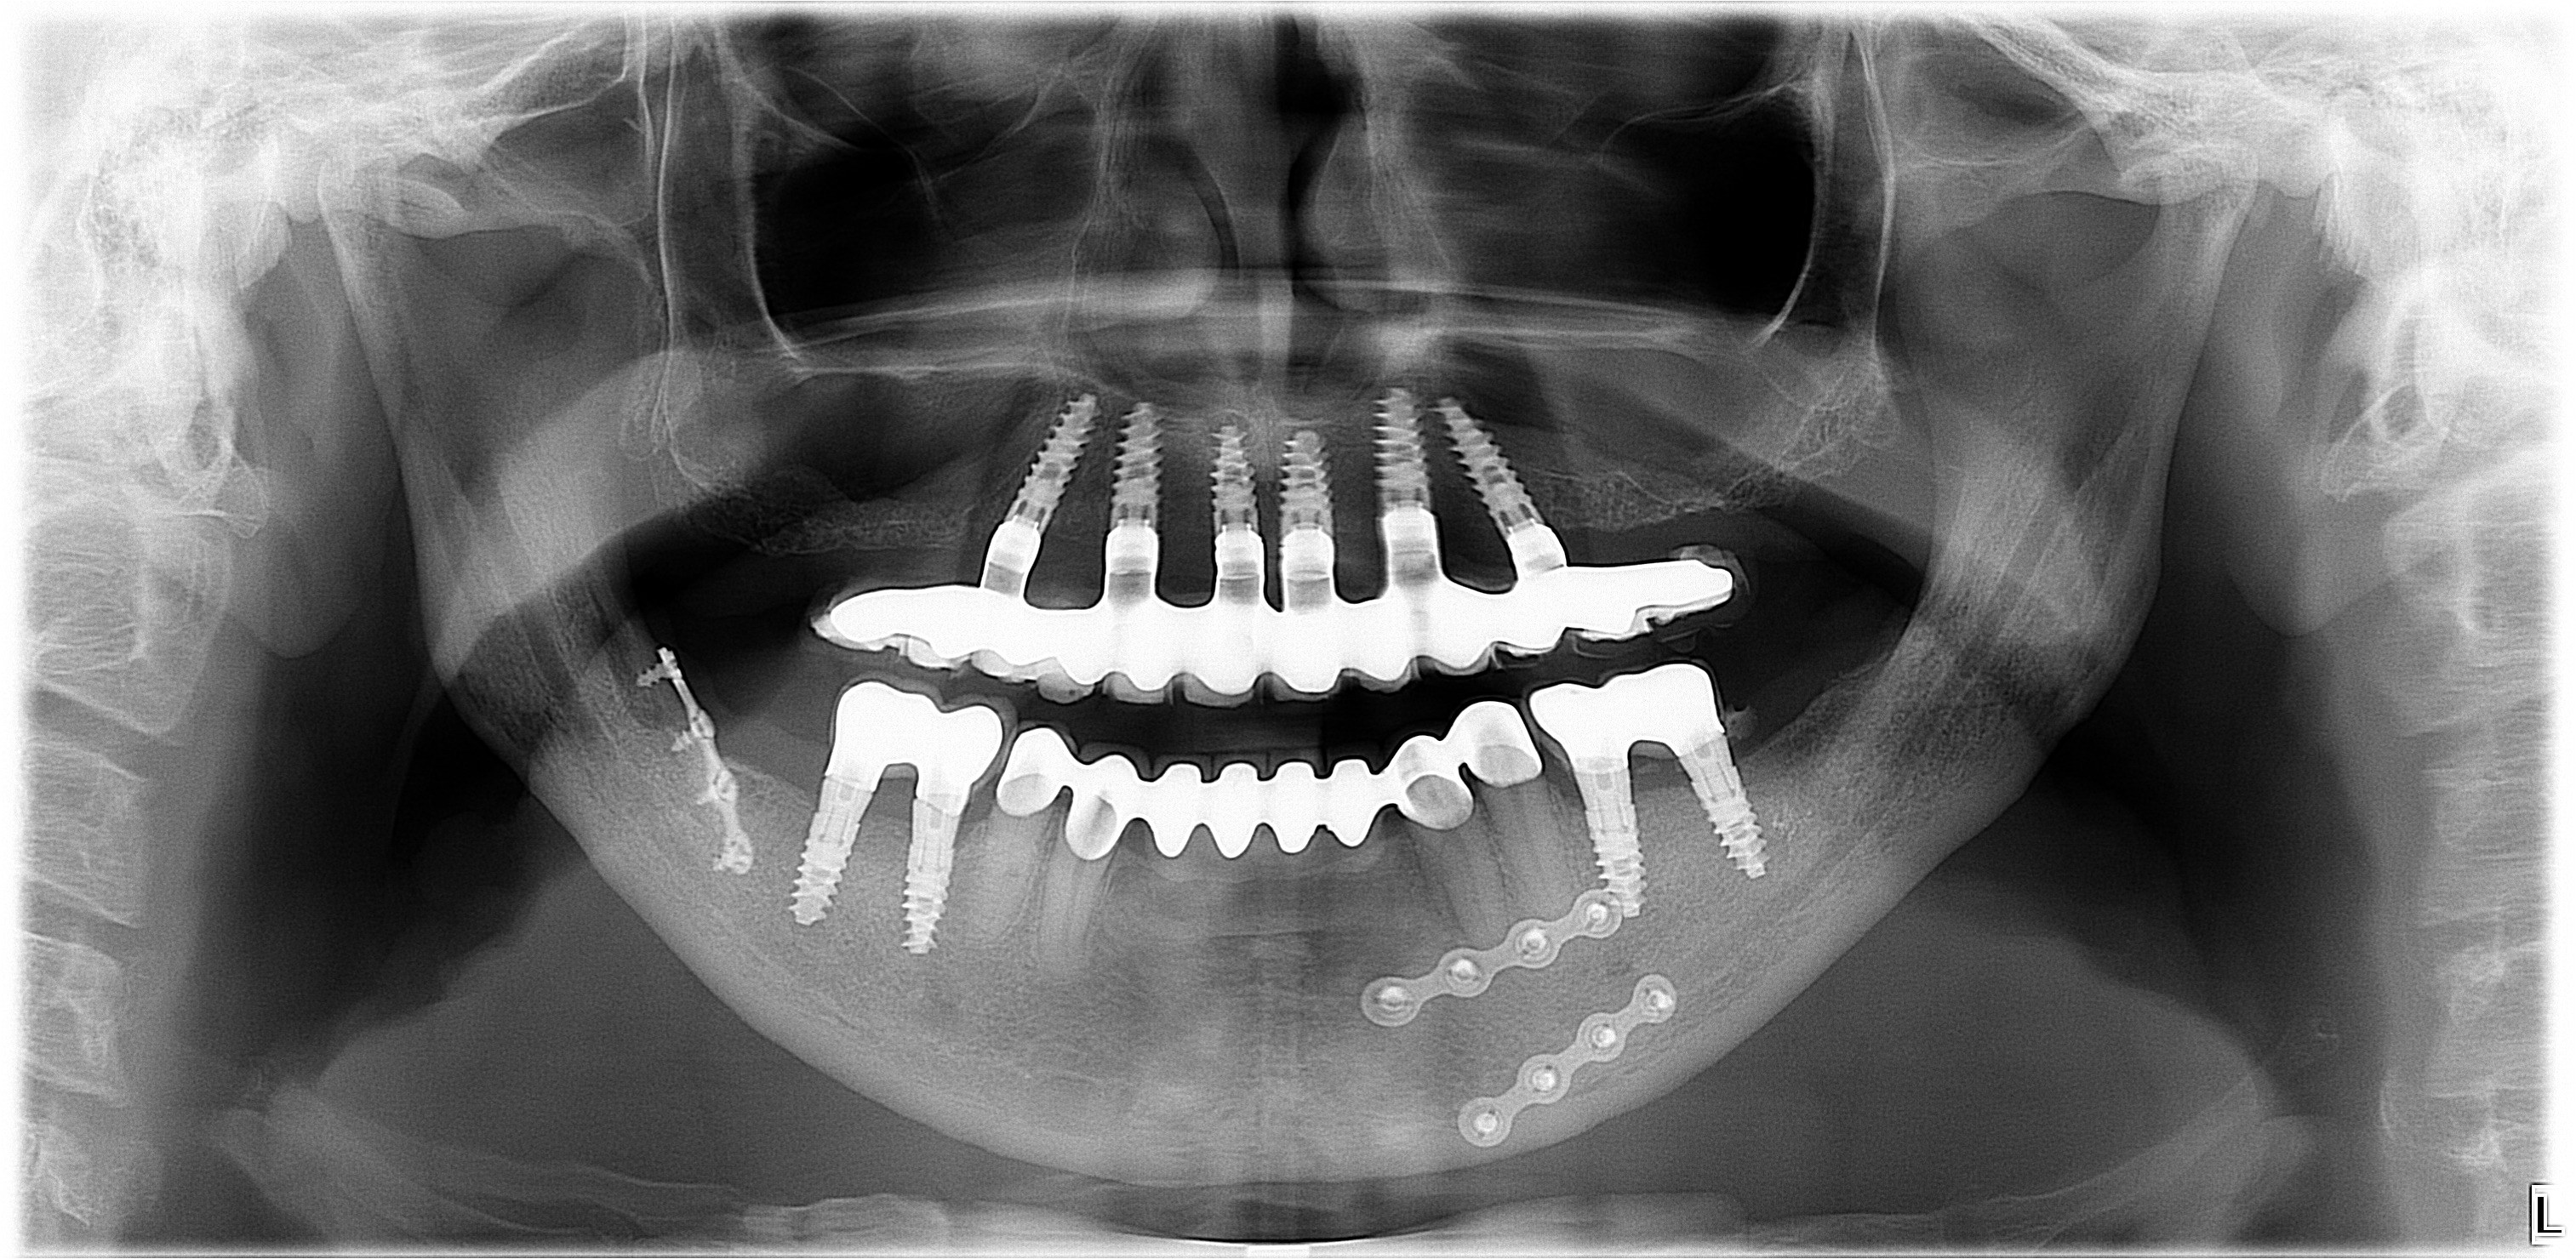

Ahogyan a képen is látható, az All-on-4 fogpótlás nem csak funkcionálisan, hanem esztétikailag is a legjobb megoldás teljes, vagy majdnem teljes foghiány esetében.

A fogászati implantátumok speciális szögben történő behelyezése miatt elkerülhető a csontpótló beavatkozás, így már maga a műtét, valamint a gyógyulás is gyorsabb.

A súlyos csontveszteség ellenére is sikerült páciensünknek fix, rögzített fogsort készíteni, a feslő állcsonton az All-on-4, míg az alsó állcsonton az All-on-6 implantációs megoldással, így visszakaphatta a rágás örömét.